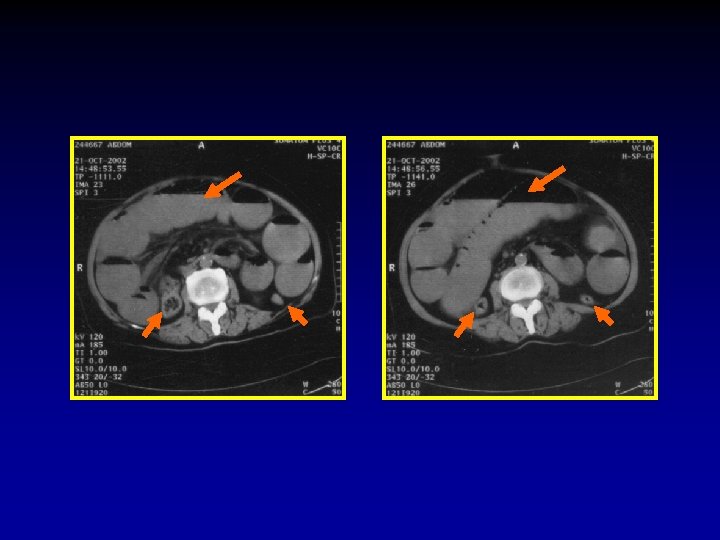

The CT signs of closed loop obstruction of the small intestine are: 1. Evidence of small bowel obstruction. 2. A U-Shaped or radial configuration of the fluid filled dilated loops. 3. At the site of obstruction, a whirl sign, beak sign, triangular loop, or two adjacent collapsed loops.

A At U-Shaped the site Evidence of configuration obstruction of. The small Whirl of two bowel theadjacent sign fluid obstruction. filled collapsed dilatedloops